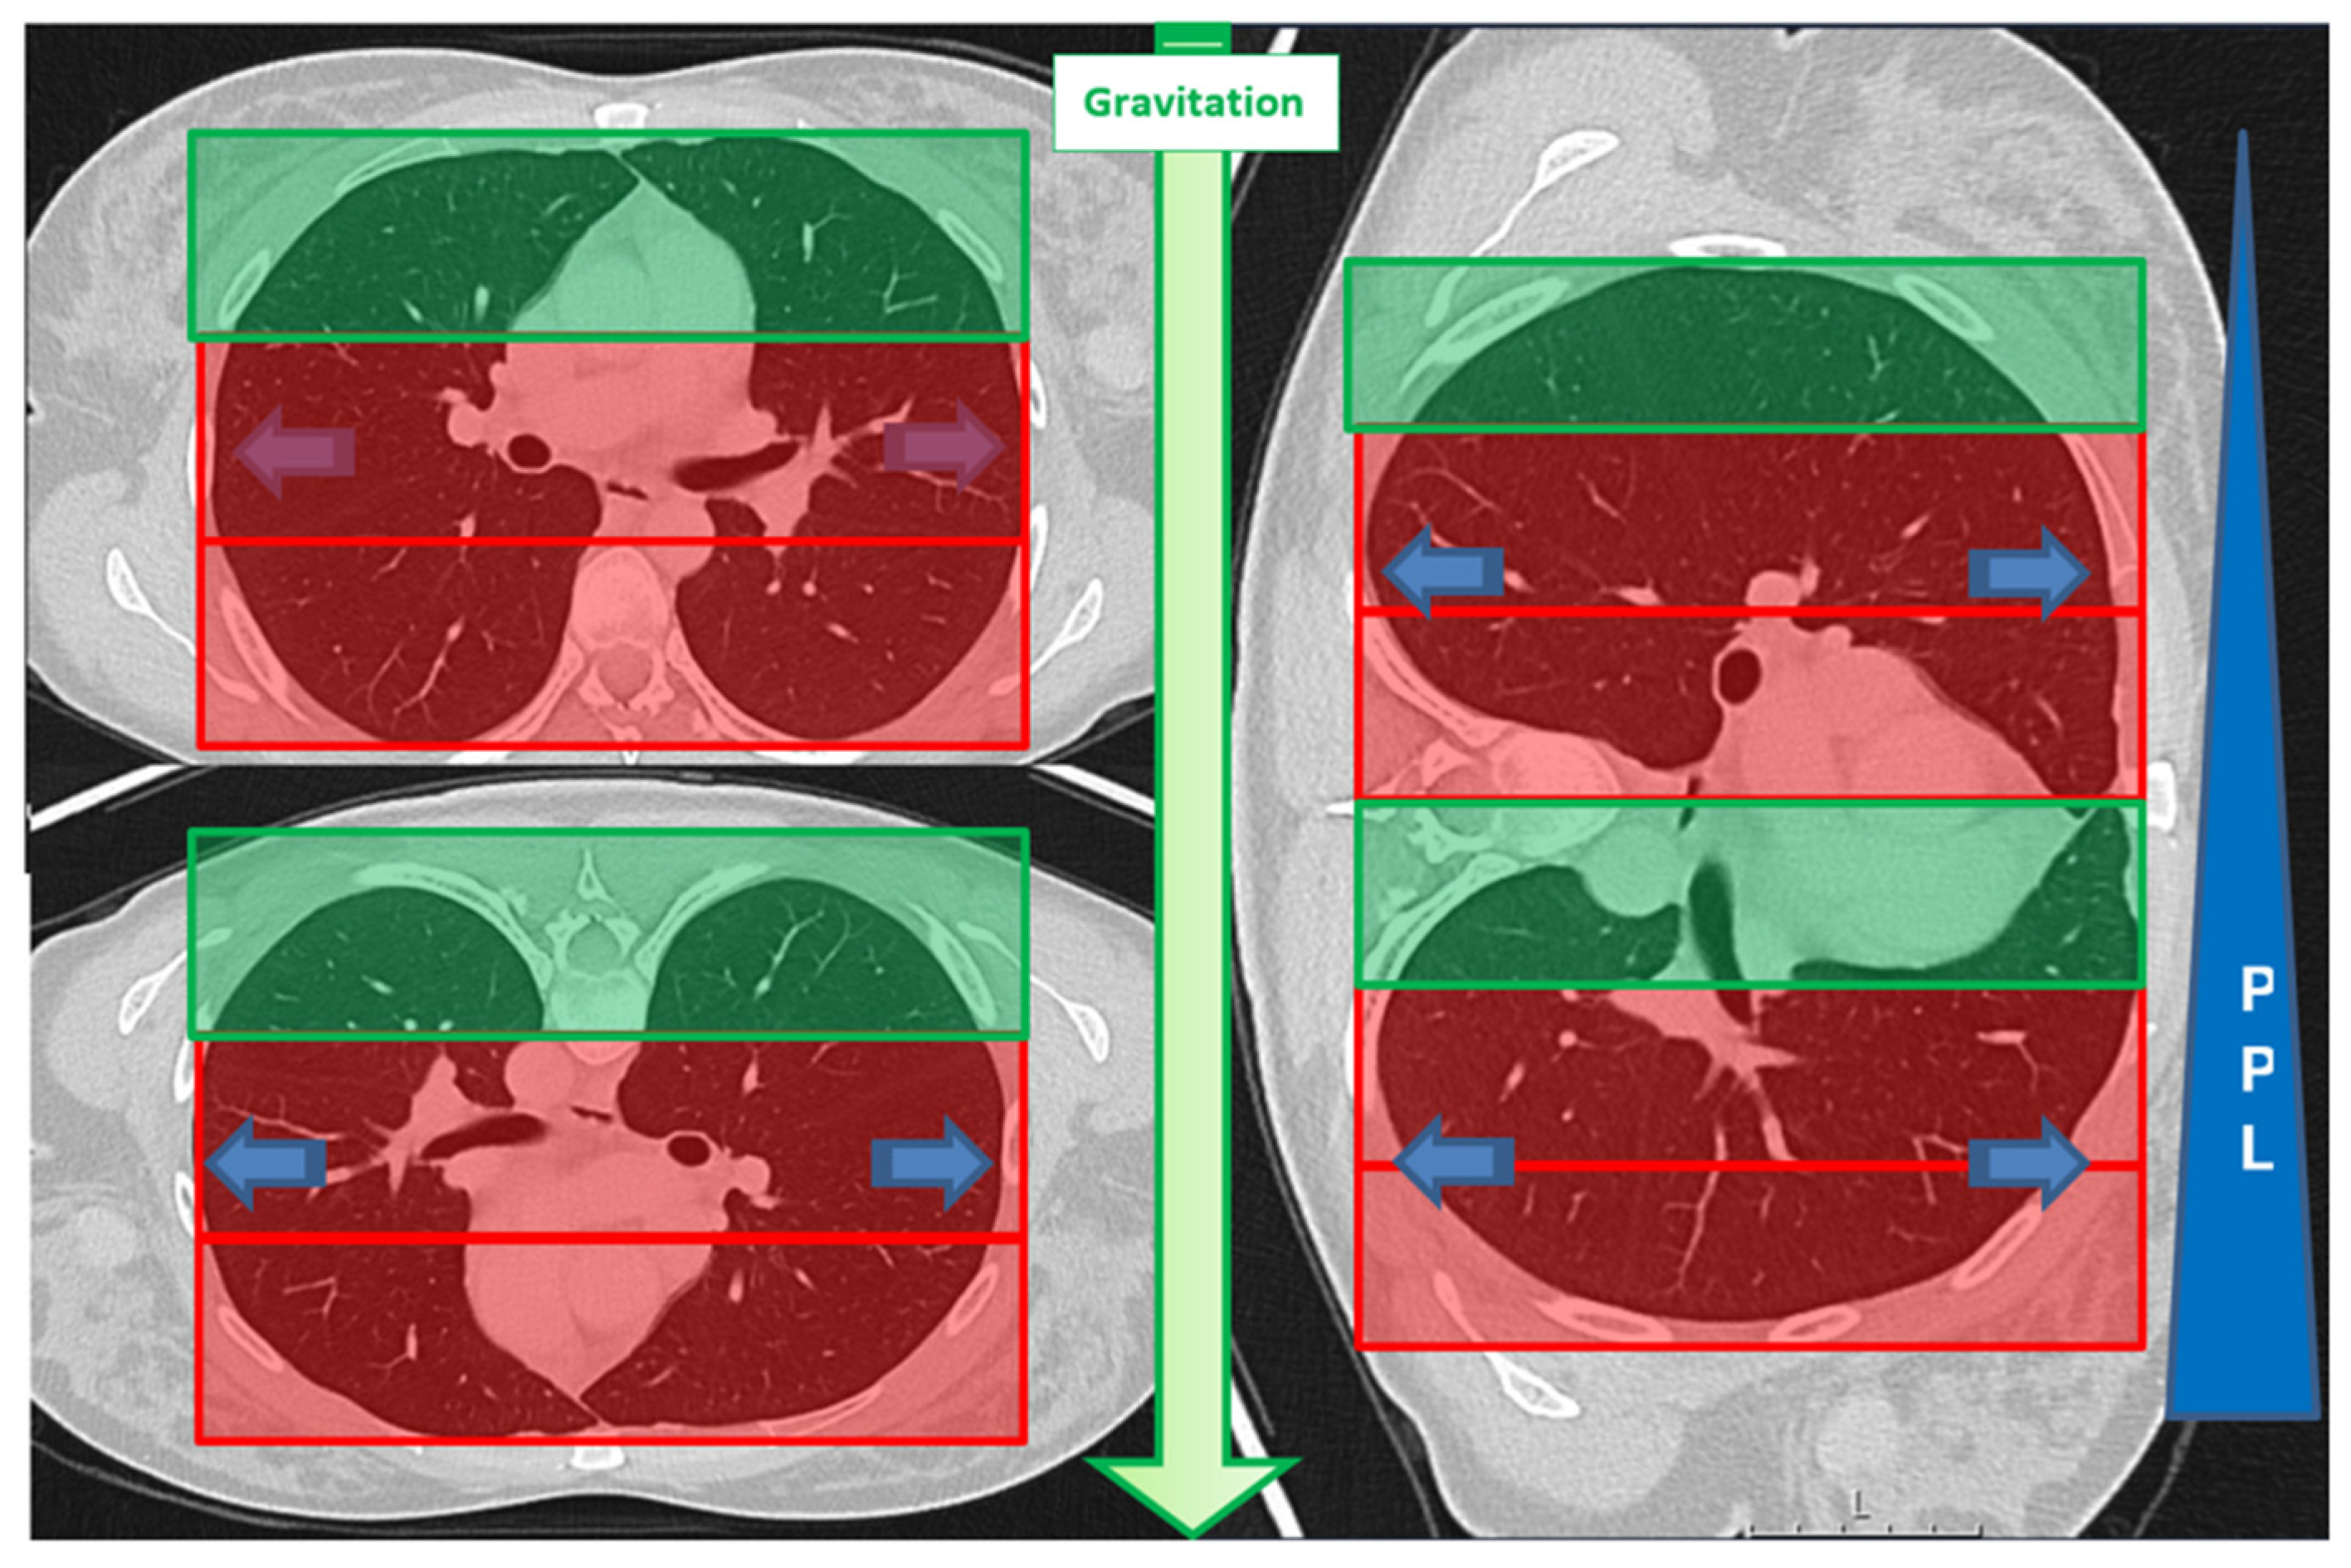

| Lesion location in D area | 53 | 46% | 34 | 40% | 19 | 63% | 0.034 * |

| Lesion location in D area | 1.402 | 0.517 | 7.369 | 1 | 0.007 * | 4.064 | 1.477 | 11.186 |

- Nyren, S.; Mure, M.; Jacobsson, H.; Larsson, S.A.; Lindahl, S.G. Pulmonary perfusion is more uniform in the prone than in the supine position: Scintigraphy in healthy humans. J. Appl. Physiol. 1999, 86, 1135–1141. [Google Scholar] [CrossRef]

- Powers, K.A.; Dhamoon, A.S. Physiology, Pulmonary Ventilation and Perfusion; StatPearls Publishing: Treasure Island, FL, USA, 2019. [Google Scholar]